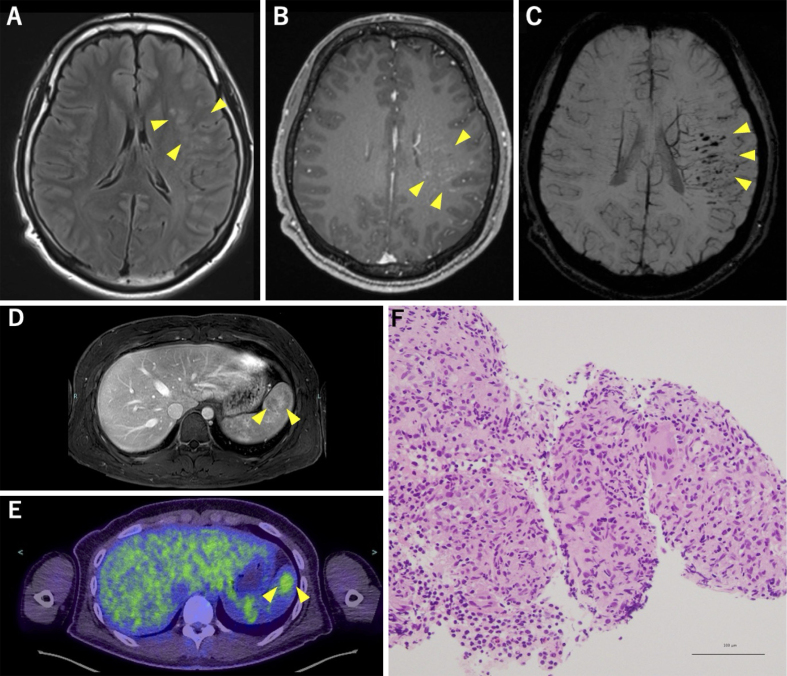

Neurosarcoidosis Limited to the Central Nervous System and Spleen, Presenting with Episodic Nonfluent Aphasia.